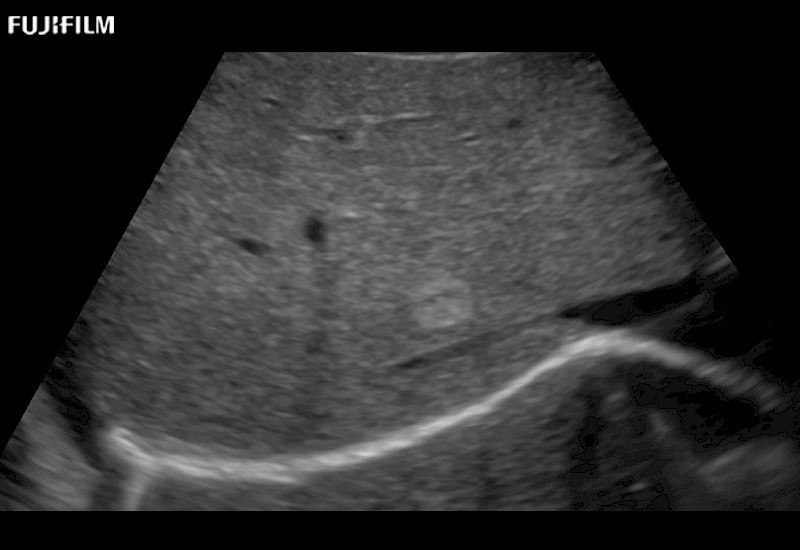

Learn moreFujifilm Healthcare continues to listen to the experts, our neurosurgeons, by developing an ultrasound system specifically designed for the Operating Room.

Guidance is the fundamental purpose for all of our surgical ultrasound technology. Fujifilm Healthcare is committed to designing tools that help neurosurgeons navigate inside the human body and provide the necessary information to immediately make critical surgical decisions.

With the ARIETTA Precision the next level of surgical ultrasound is here.